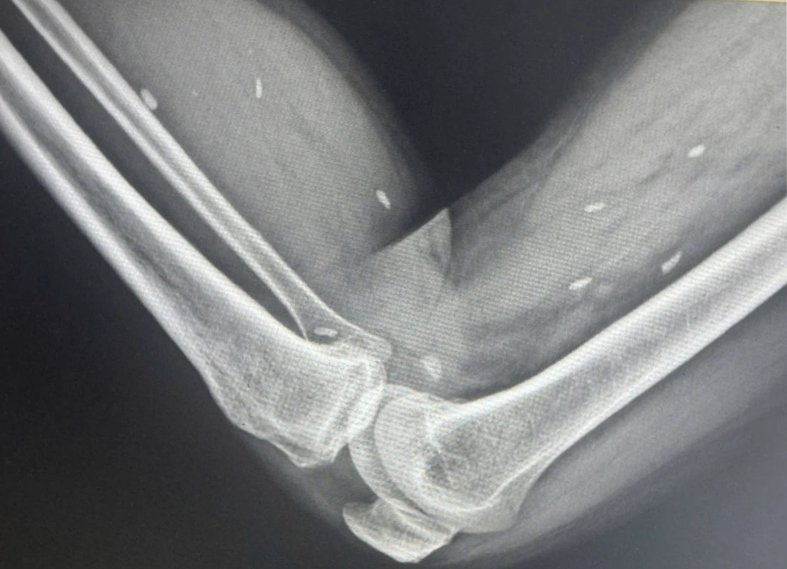

Kết quả cho thấy nhiều kén sán có kích thước tương đương hạt gạo, nằm rải rác trong các mô mềm vùng xương đùi và cẳng chân. Bác sĩ nhận định đây là hình ảnh điển hình của tình trạng nhiễm kén sán.

Hình ảnh trên phim X-quang. Ảnh: BVCC.